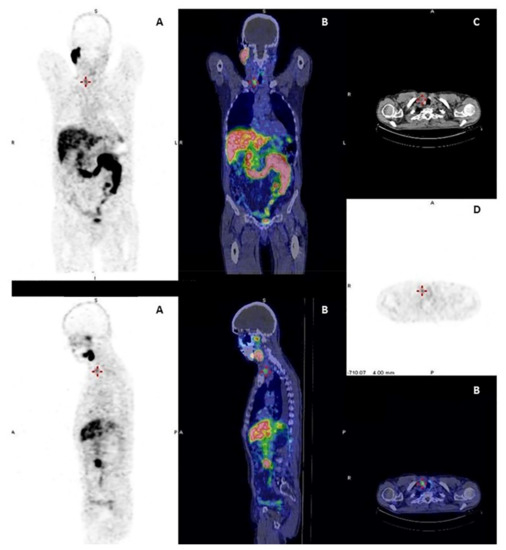

Figure 1.

Papillary thyroid cancer in a 41-year-old man with a high thyroid stimulating hormone stimulated serum thyroglobulin level (475 ng/mL). Post-therapy (A) 131I whole-body scan showed pulmonary uptake and uptake and in neck lymph nodes. 18F-FDG PET-CT (B,C,D): CT images evidenced multiple small millimetric lung metastases (B,C,D), without significant 18F-FDG uptake.

In DTC patients, the “flip-flop phenomenon” consists of a mismatch between high glucose and low iodine uptake, due to the elevated glucose metabolism coupled to the dedifferentiation process and has an important prognostic significance (Figure 2). This is observed in patients with iodine refractory thyroid cancer, with poorly differentiated, Hürthle cell cancer, PTC with aggressive features (tall cell variant) or with the BRAF V600E mutation and less frequently in patients with well differentiated papillary or follicular carcinoma. This indicates clinically more aggressive lesions [74,75,76] and the presence of 18F-FDG uptake in lesions with also radioiodine uptake indicates that these lesions are less likely to respond to radioiodine treatment [77].

Figure 2.

Papillary thyroid cancer in a 30-year-old woman. Post-therapy (A) 131I whole-body scan and 18F-FDG PET-CT (B,C,D) images. Post-therapy 131I whole-body scan did not show areas of uptake (A). 18F-FDG PET-CT images evidenced multiple areas of increased uptake in the left retrosternal and latero-cervical region.